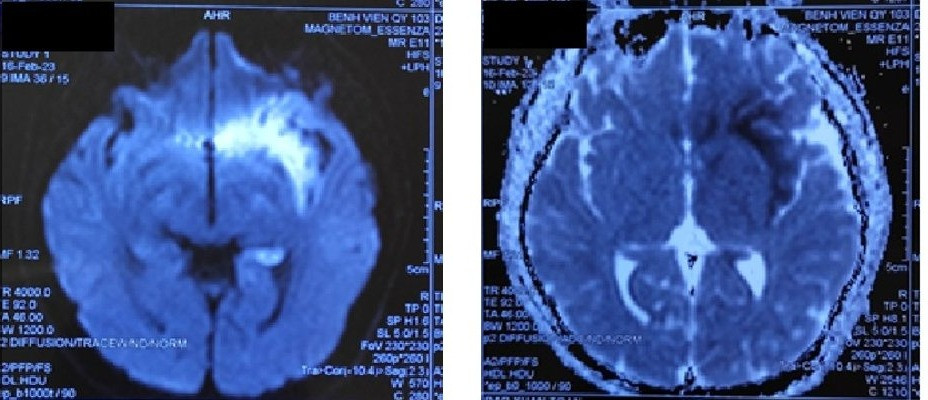

Kết quả khám lâm sàng, xét nghiệm cho thấy bệnh nhân có các tổn thương viêm não - màng não vùng thùy đảo, trán thái dương bên trái. Bệnh nhân được chẩn đoán viêm não - màng não do Herpes simplex virus (HSV).